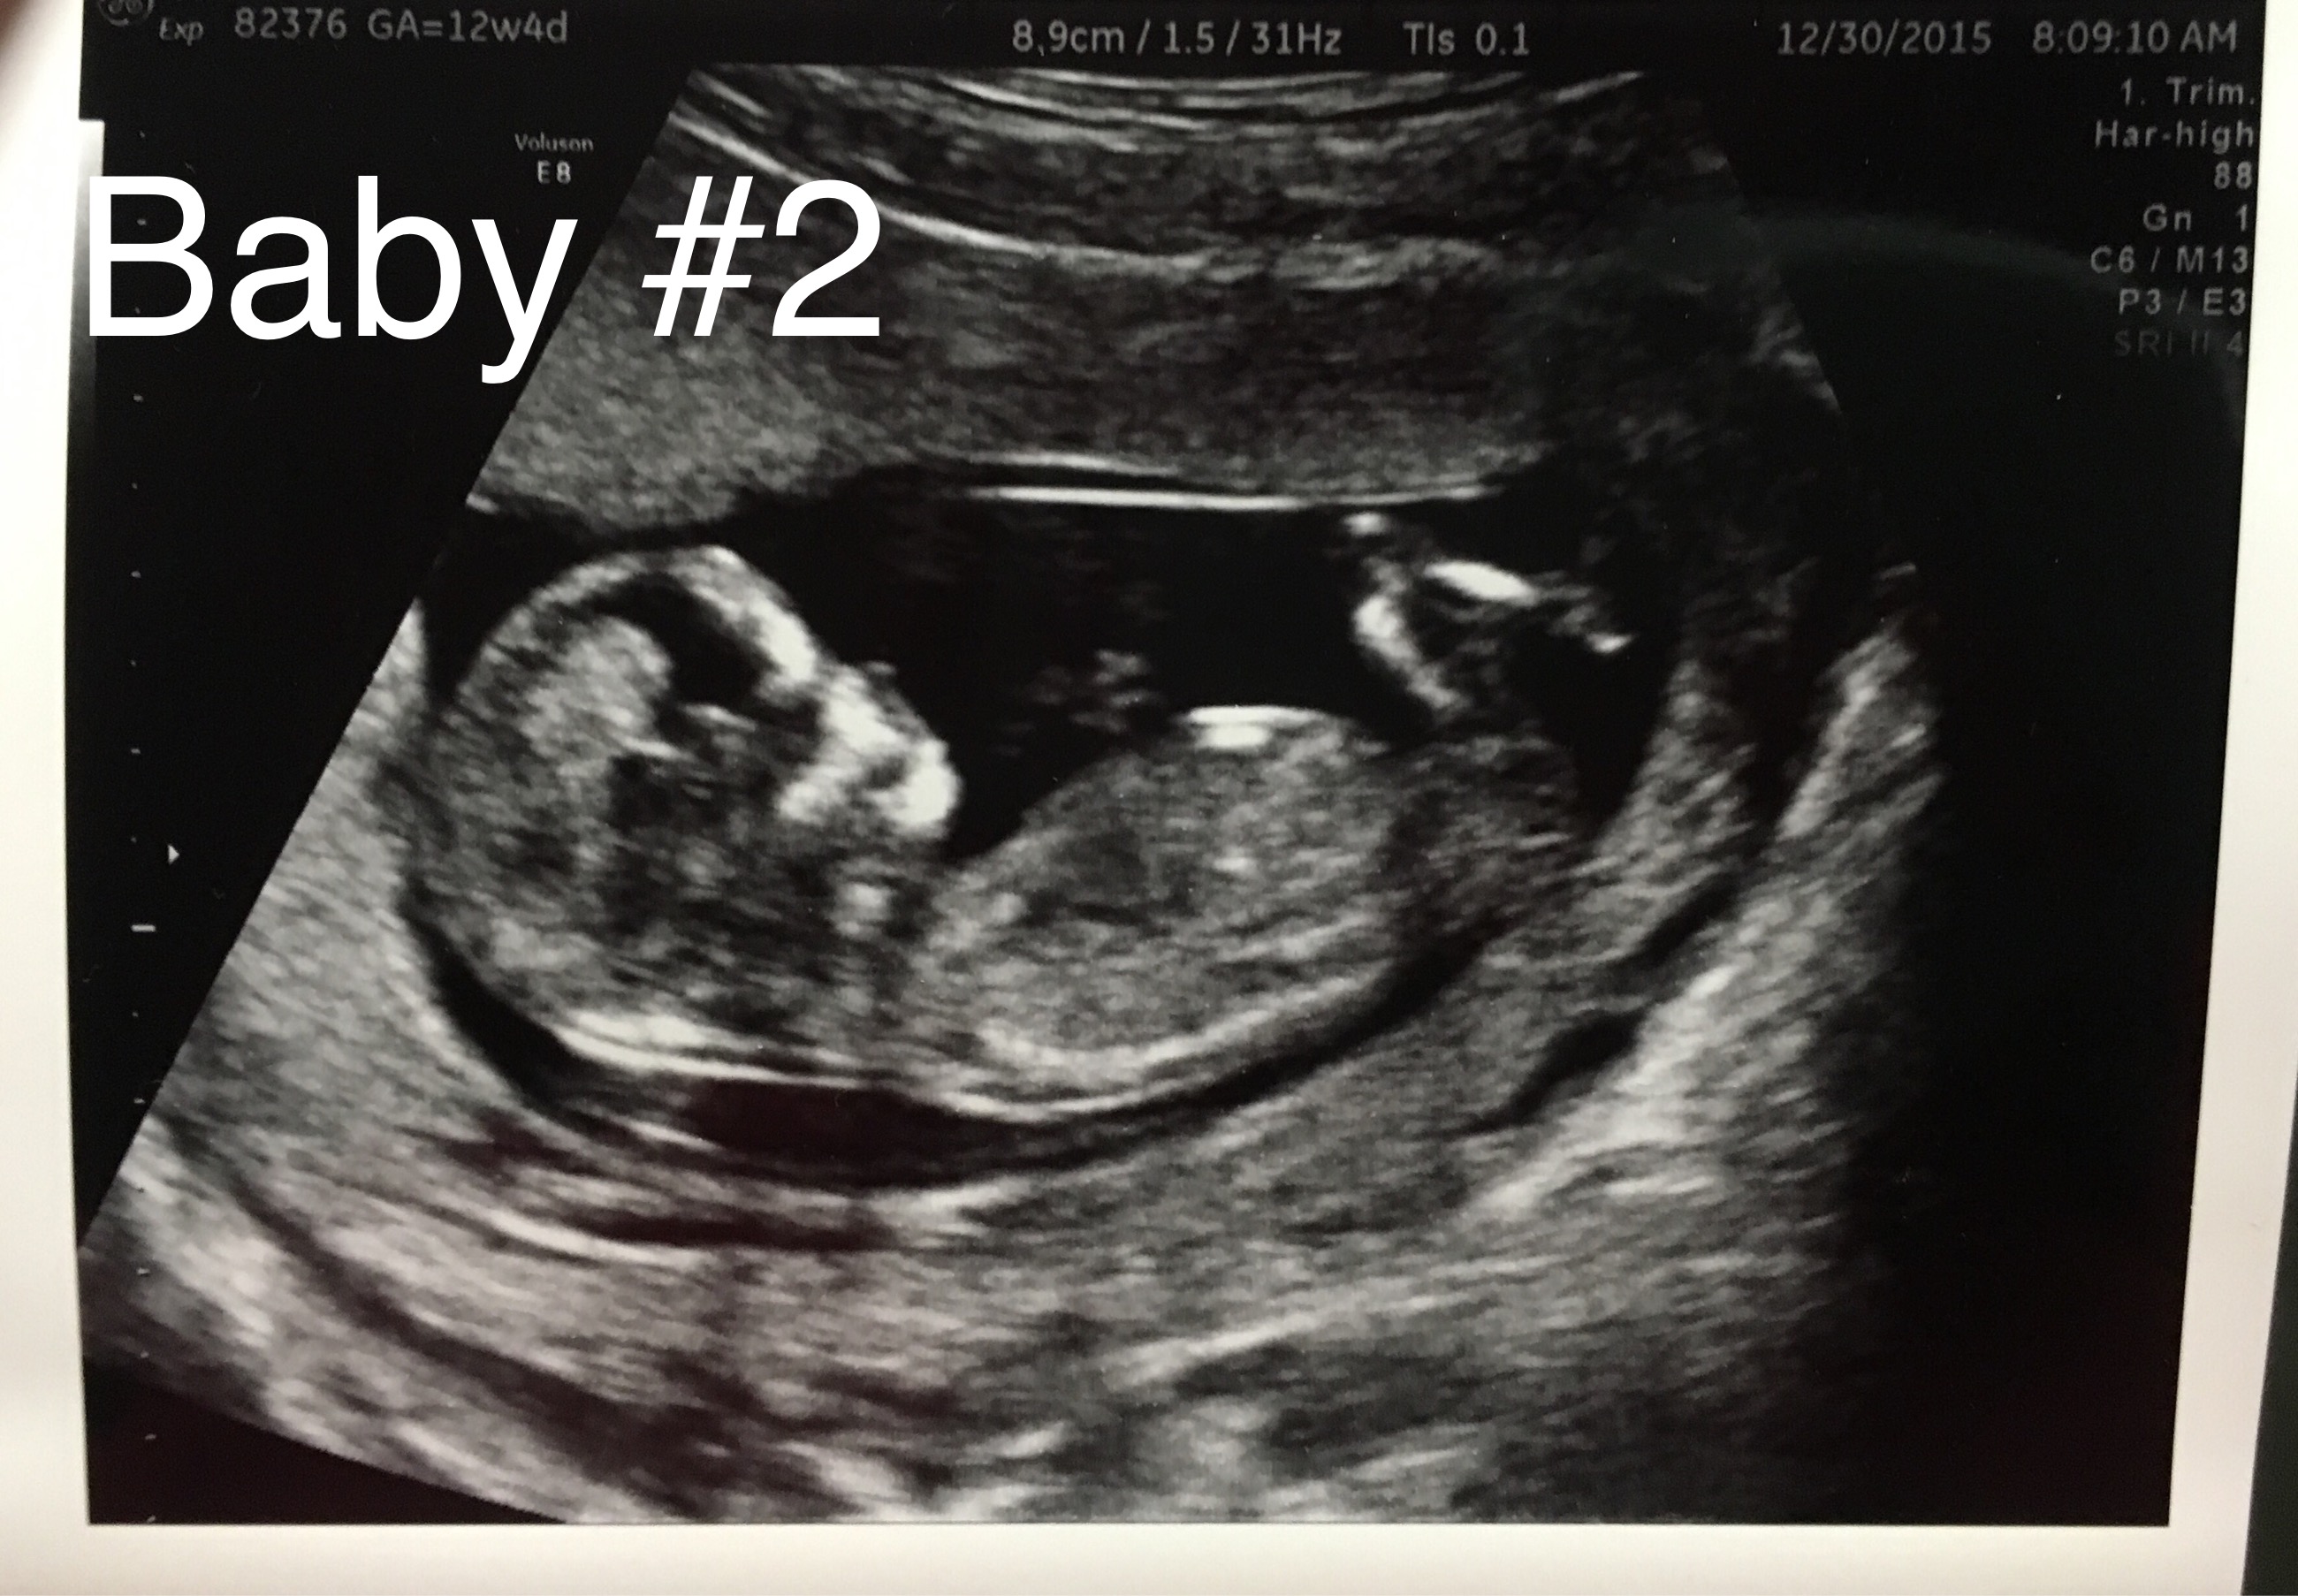

You had an ultrasound and the ultrasound sonographer told you that they're suspicious of a boy. Interesting to note, the doppler actually has higher levels of. Here's my experience with just that! However, compared to dating according to menstrual cycle, the ultrasound would be more accurate. The 12 weeks ultrasound examination can be done from 11 weeks 4 days to 13 weeks 6 days. Gender confirmed by harmony test! 12 weeks 5 days ultrasound/ gender reveal. Gender can be determined by ultrasound as early as 12 weeks in some cases. 12 weeks is little early but sometimes the gender can be seen. Ramzi theory explained by ultrasound technicians. Check out our 12 week ultrasound, where we find out the gender of our baby! My mom bawled her eyes out and you can hear. Is she spot on or should we wait until around 20 weeks to make sure?

You mentioned that you're 12 weeks along. Whats the accuracy of sonographic determination of fetal gender study. Gender can be determined by ultrasound as early as 12 weeks in some cases. 12 week ultrasound gender ultrasound gender prediction ultrasound tech ultrasound pictures boy or can an ultrasound reveal gender at 12 weeks? 19 week gender scan accuracy. I had my 12 week ultrasound yesterday, and my tech suggested looking up the nub… read post. Including the blood tests improve the overall accuracy of screening for down syndrome. Gender detect by us after 33 weeks in position of placenta posterior upper segementt grade ii maturity.heart beat 149.in 26 week us report.